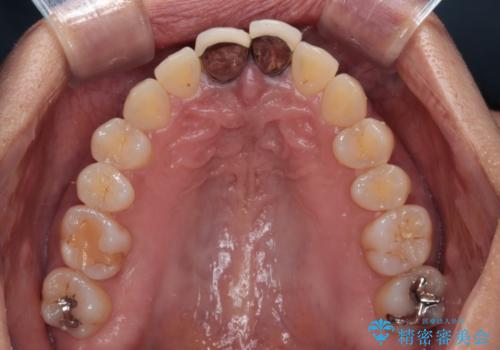

- 前歯のクラウン付近の歯肉が黒く見えることを気にして来院された患者様です。

10年以上前に根管治療を行っており、その際にはラバーダムを使用してしっかりと治療を行っていたとのことで、今回は根管治療は行わずに土台のみを作り替えた上で、オールセラミッククラウンにて補綴治療を行うこととしました。